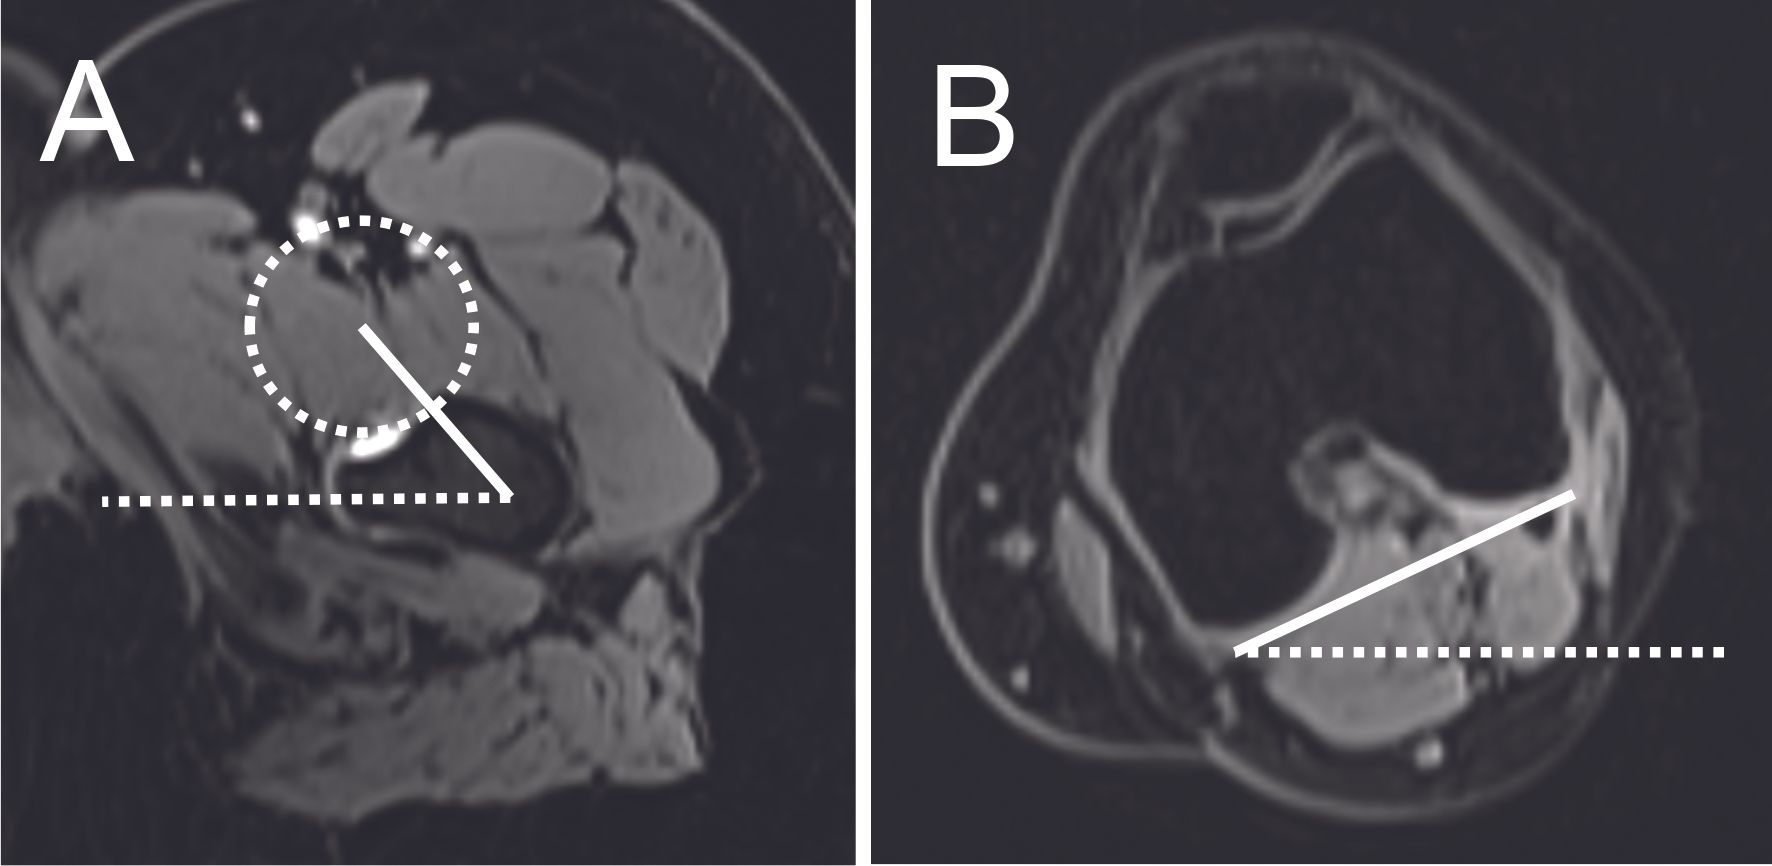

Measurement of femoral torsions by MRI or CT scan is essential (Figure 8). There are many methods of calculating torsions (5), of which Murphy's method is the most reproducible. A femoral torsion problem can be a cause of FAI (6). Femoral retroversion (<0°) may result in an anterior FAI, between the anterior-inferior iliac spine and the proximal femur. Increased femoral anteversion (>35°) may result in posterior ischiofemoral FAI between the lesser or greater trochanter and the ischial tuberosity.